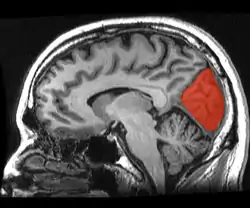

![]() Sagittal MRI slice with the cuneus and lingual gyrus shown in red. | |

The cuneus (from Latin 'wedge'; plural cunei) is a smaller lobe in the occipital lobe of the brain. The cuneus is bounded anteriorly by the parieto-occipital sulcus and inferiorly by the calcarine sulcus.